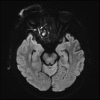

Invasive fungal sinusitis causes painful orbital apex syndrome with ophthalmoplegia and visual loss; the mechanism is unclear. We report an immunocompromised patient with invasive fungal sinusitis in whom the visual loss was due to posterior ischaemic optic neuropathy, shown on diffusion-weighted MRI, presumably from fungal invasion of small meningeal-based arteries at the orbital apex. After intensive antifungal drugs, orbital exenteration and immune reconstitution, the patient survived, but we were uncertain if the exenteration helped. We suggest that evidence of acute posterior ischaemic optic neuropathy should be a contra-indication to the need for orbital exenteration in invasive fungal sinusitis.